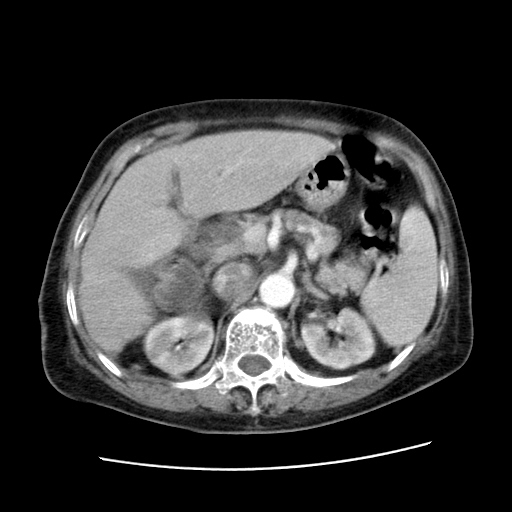

女,77.无不适

肝内胆管扩张,胆囊炎,胆囊窝积液。 右侧胸腔少量积液。

肝右叶肝内胆管结石并肝内胆管扩张

胆总管扩张

肝旁多发胆囊状液体影考虑肠腔积液基中部分囊状景不多外胆囊

肝右叶肝内胆管结石并肝内胆管扩张。胆总管下段梗阻,考虑壶腹部占位。

右侧肝内胆管局限性扩张,其内密度不均匀,扩张的胆管壁增厚,考虑肝内胆管炎合并结石可能性大